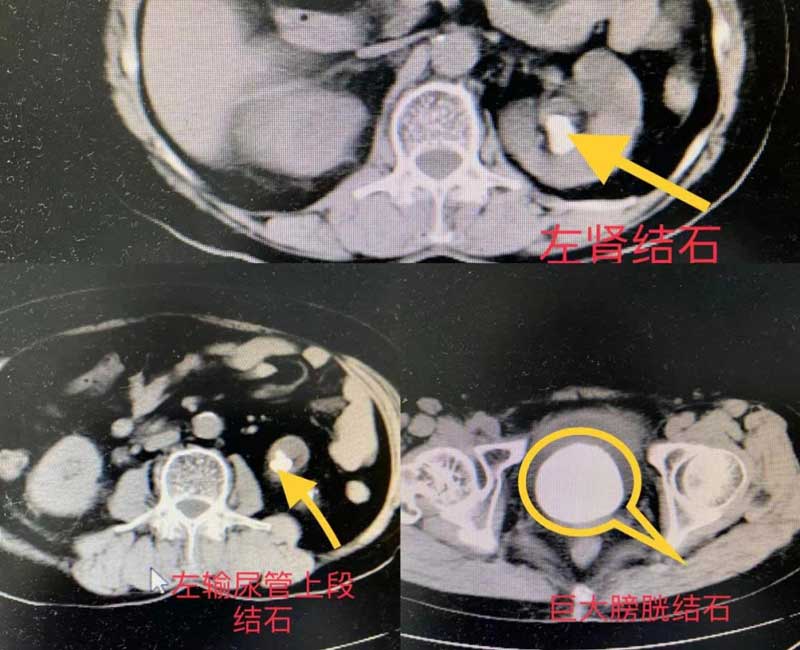

入院诊断:1.感染性休克;2.脓毒血症;3.左肾、输尿管结石併积水和感染;4.膀胱结石;5、慢性膀胱炎。

经全科讨论后,考虑患者感染重,结石复杂,故急诊行左肾穿刺造瘘术,留置导尿,术后经积极抗感染治疗后,10天后二期同时行左侧PCNL+膀胱结石碎石术,术中采用斜侧卧位,考虑膀胱结石大,在持续行膀胱结石碎石过程中(膀胱结石碎石时间4小时),同时在左腰部用另一台钬激光碎石机行双通道下左侧经皮肾镜碎石术,经皮肾镜碎石手术时间大约1.5小时。